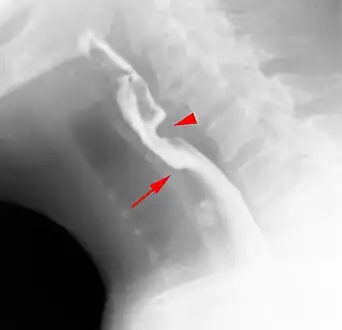

The diagnostic test of choice is a barium swallow.

Esophageal webs are thin 2–3 mm (0.08–0.12 in) membranes of normal esophageal tissue consisting of mucosa and submucosa that can partially protrude/obstruct the esophagus. They can be congenital or acquired. Congenital webs commonly appear in the middle and inferior third of the esophagus, and they are more likely to be circumferential with a central or eccentric orifice. Acquired webs are much more common than congenital webs and typically appear in the cervical area (postcricoid).

Clinical symptoms of this condition are selective (solid more than liquids) dysphagia, thoracic pain, nasopharyngeal reflux, aspiration, perforation and food impaction (the last two are very rare).